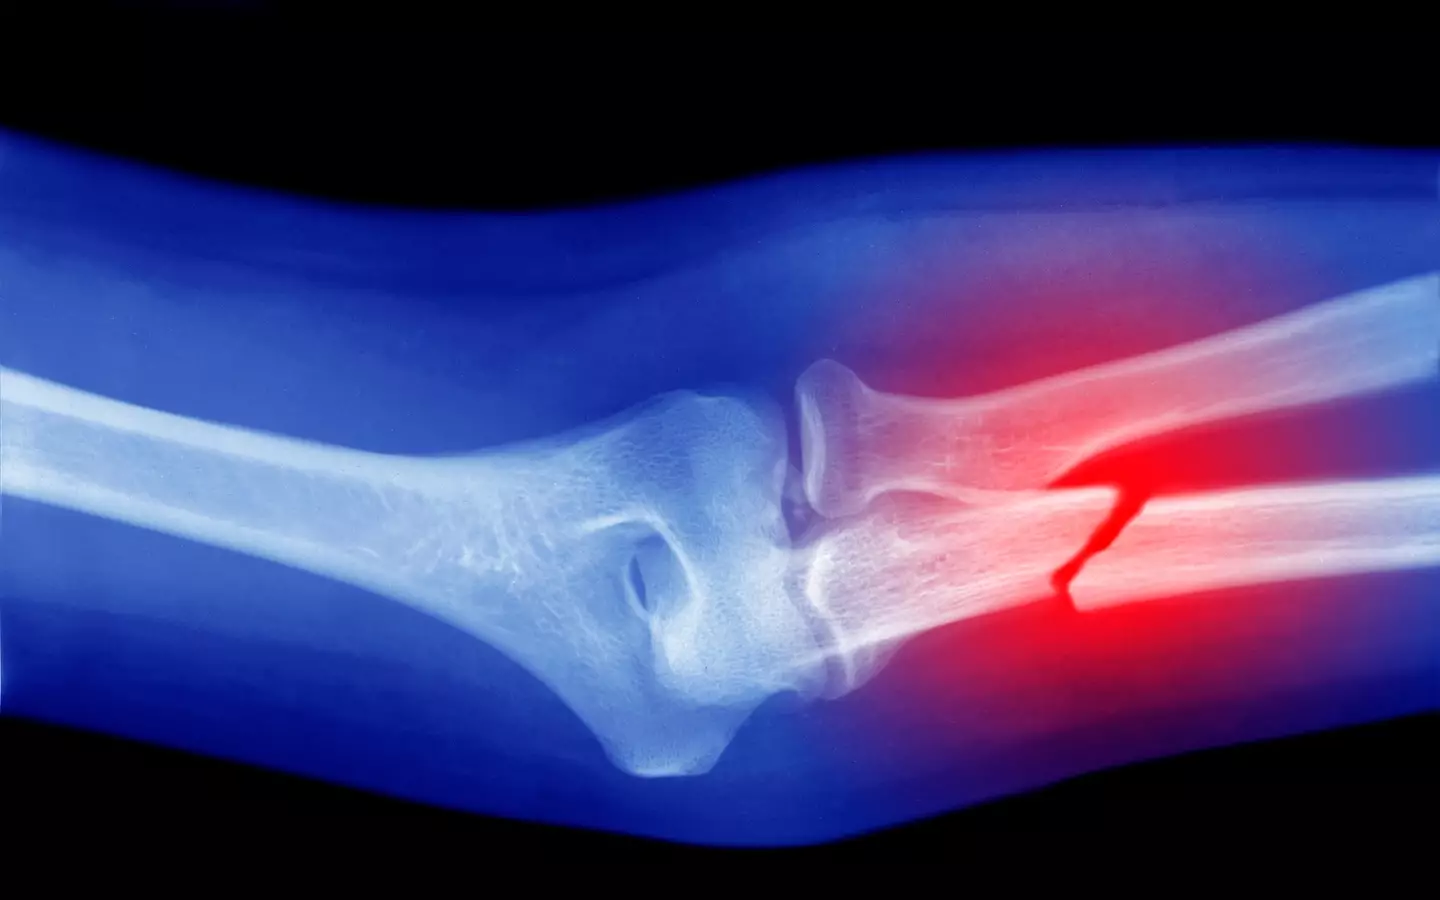

Unfortunately, Avery disclosed that she is now dealing with osteoporosis, which she suspects is linked to her use of Ozempic.

Osteoporosis is characterized by weakened and brittle bones, making them susceptible to fractures from minor impacts or stresses. According to the Mayo Clinic, it’s a condition that over 10 million Americans, primarily those over 50, contend with.

The symptoms of osteoporosis can include persistent back pain, reduced height over time, a stooped posture, and bones that fracture more easily than anticipated.